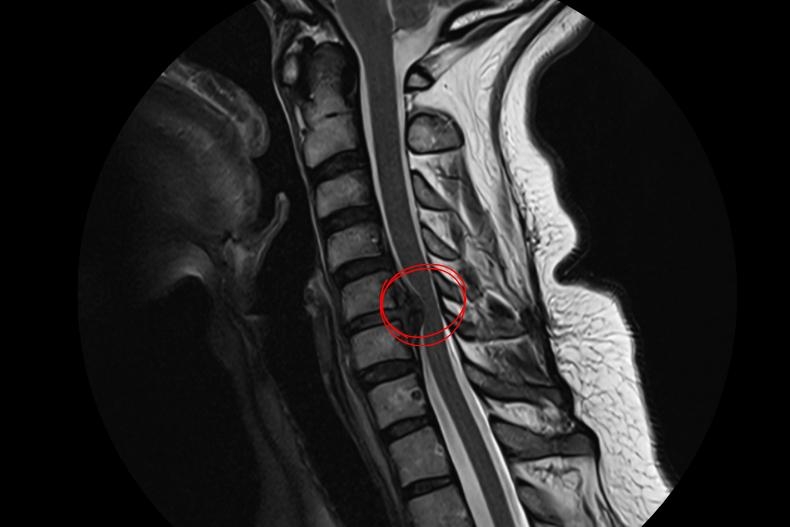

Cervical Disc Herniation Surgery: Neurological Safety Through Minimal Intervention

Cervical disc herniation requires a high level of surgical precision due to its proximity to the spinal cord and nerve roots. Despite advances in imaging, not every cervical disc protrusion necessitates surgical treatment. Clinical symptoms, neurological examination findings, and radiological data must be evaluated together.

According to the Less Is One strategy:

- Surgery is planned only in cases of progressive neurological deficit or symptoms resistant to conservative management.

- Unnecessary multi-level surgeries are avoided, favoring focused interventions targeting the symptomatic level.

- In suitable patients, minimally invasive anterior approaches are preferred; when more than two levels are involved, posterior approaches may be selected. In selected posterior cases, instrumentation may not be required.

This strategy minimizes surgical complications while preserving spinal cord and nerve integrity, leading to better functional outcomes.